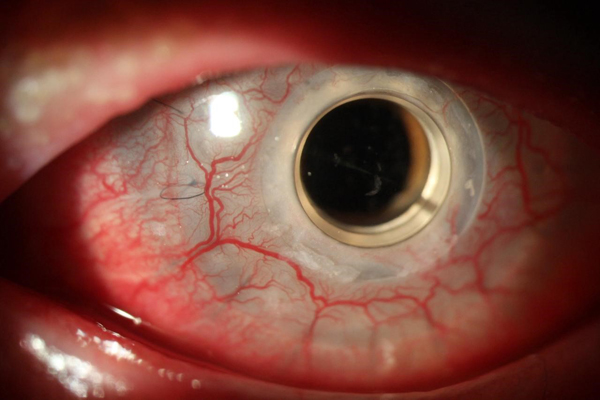

Bilateral Boston Keratoprosthesis for treatment of a variant of keratitis–ichthyosis–deafness syndrome